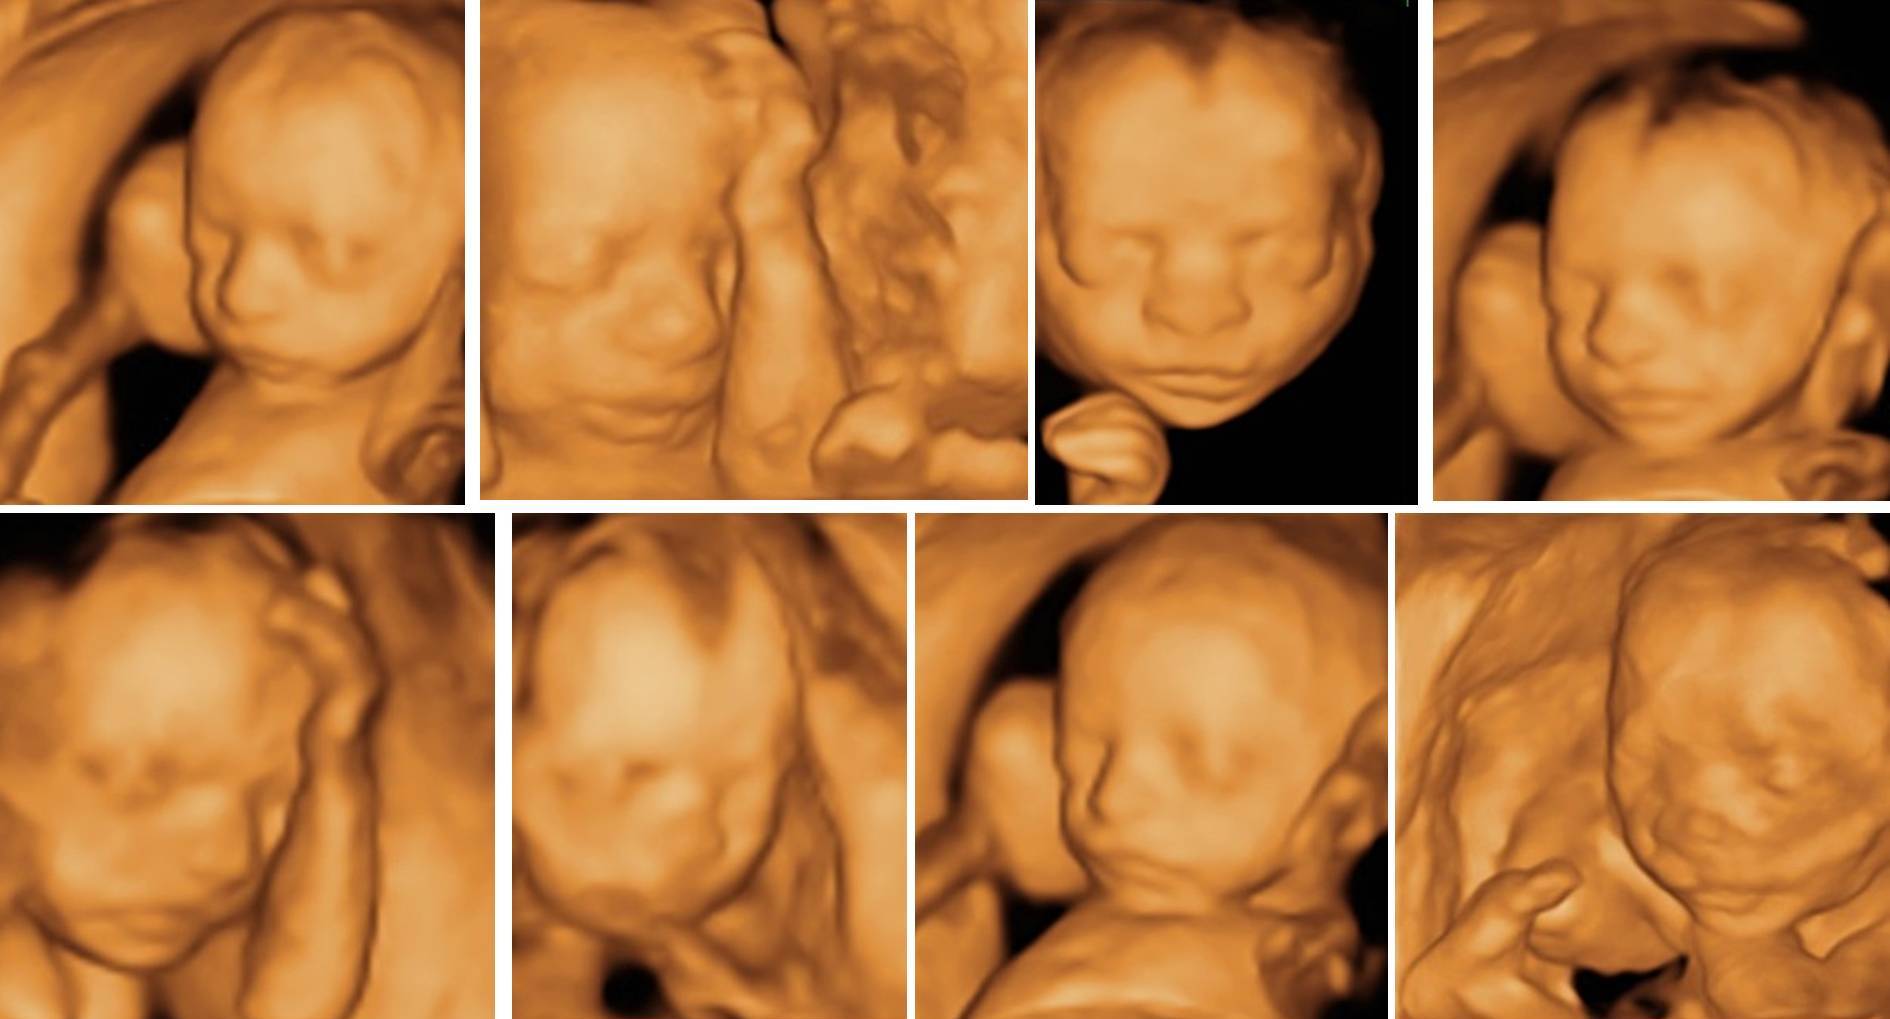

The baby in the womb shows different behavioral and movement characteristics, and these characteristics can be detected with 4D ultrasound. The 6th-7th months of pregnancy are the period when 4D ultrasound images can be taken, where families can understand what their babies look like.

It is possible to closely monitor all the movements of the baby, such as sucking the thumb, stretching the feet, smiling, grimacing, opening and closing the eyes, with 4D ultrasound.

Parents can enjoy realistic and clear images of their baby throughout their entire pregnancy. So when is the ideal time to have a 4D ultrasound? The answer to this question depends on what the patient wants to see. For example, in the early stages of your pregnancy, the mother can see the baby’s entire body because it is so small. There is not much detail in the facial area. But the baby’s movements can be seen a little. Between 24 and 32 weeks, mothers will see the baby’s facial features best and will be able to follow the movements. After 32 weeks, you won’t see much movement (because: the mother’s belly can only stretch so far and the baby won’t move much). Also, depending on the position, it can be difficult to get good photos of the baby. But you can see the baby’s chubby and more detailed face. The best option for a mother is to have sessions at different 3-month intervals. However, if the mother only wants one session, it is ideal to do it from 24 to 32 weeks.

Any time after the end of the first trimester is suitable, but the clearest images of the baby are obtained between 24 and 32 weeks. In addition to gestational age, the quality of the 3D/4D image can vary depending on the baby’s position in the womb and the level of amniotic fluid surrounding the baby. Here are examples of 3D ultrasounds at various ages.